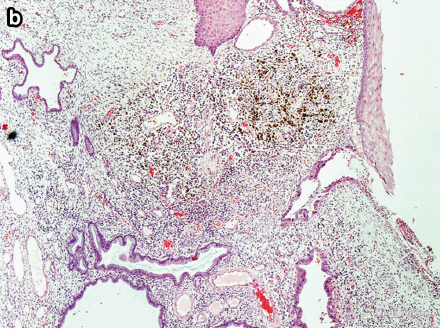

初步诊断为宫颈息肉 全麻下行肿物切除术,并将肿块基底部广泛切除 肉眼观为90*50*35mm带蒂肿块,有囊性部分和出血部分 病理提示为宫颈粘膜息肉,有子宫内膜基质和少数的内膜腺体

这个病例主要是提出来鉴别一下宫颈息肉和子宫内膜异位症,临床症状后者有周期性的出血比较重要,但是只从临床症状或者外观上还是不确定的,最好还是手术切除病灶做活检。